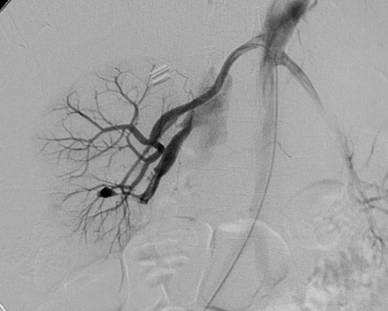

這題的解題核心在於結合病史(腎臟切片後血尿)與影像學檢查(腎動脈血管攝影)的特徵。圖片中最關鍵的視覺線索是腎臟內動脈分支處有顯影劑外溢形成囊狀結構,且同時有靜脈提早顯影,這強烈暗示血管損傷。